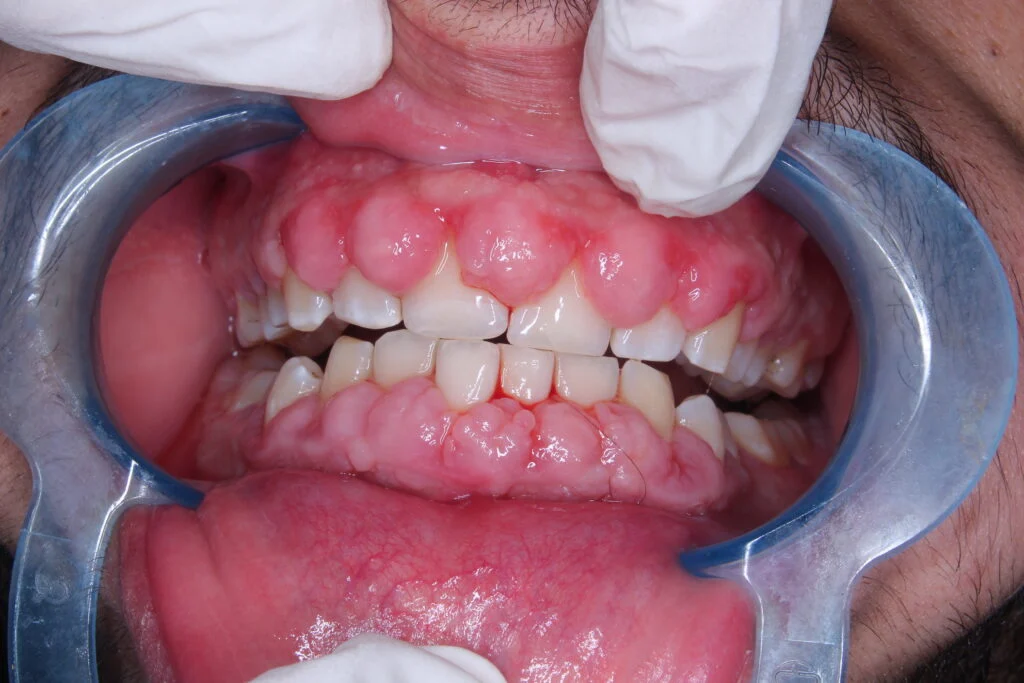

Gums over teeth

Swollen Gum can look unattractive. With other causes of swollen gum, you may experience localized red, swollen gums. They can also be painful and are likely to bleed. Since most swollen gum are inflammatory in nature and are dangerous to your teeth and bones. In all cases, gum swelling can trap bacteria, tartar, and irritants under the gum line, leading to accelerated decay and more irritation.